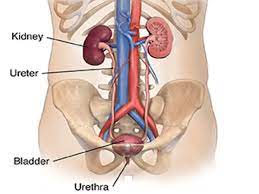

قیمت: 69٬000 تومان - دسته بندی فایل: علوم پزشکی

قیمت: 69٬000 تومان - دسته بندی فایل: علوم پزشکیپاورپوینت کلیه و مجاری ادراری (ppt) 71 اسلاید

فروش ویژه پاورپوینت حرفه ای کلیه و مجاری ادراری / تعداد اسلاید: 71 اسلاید